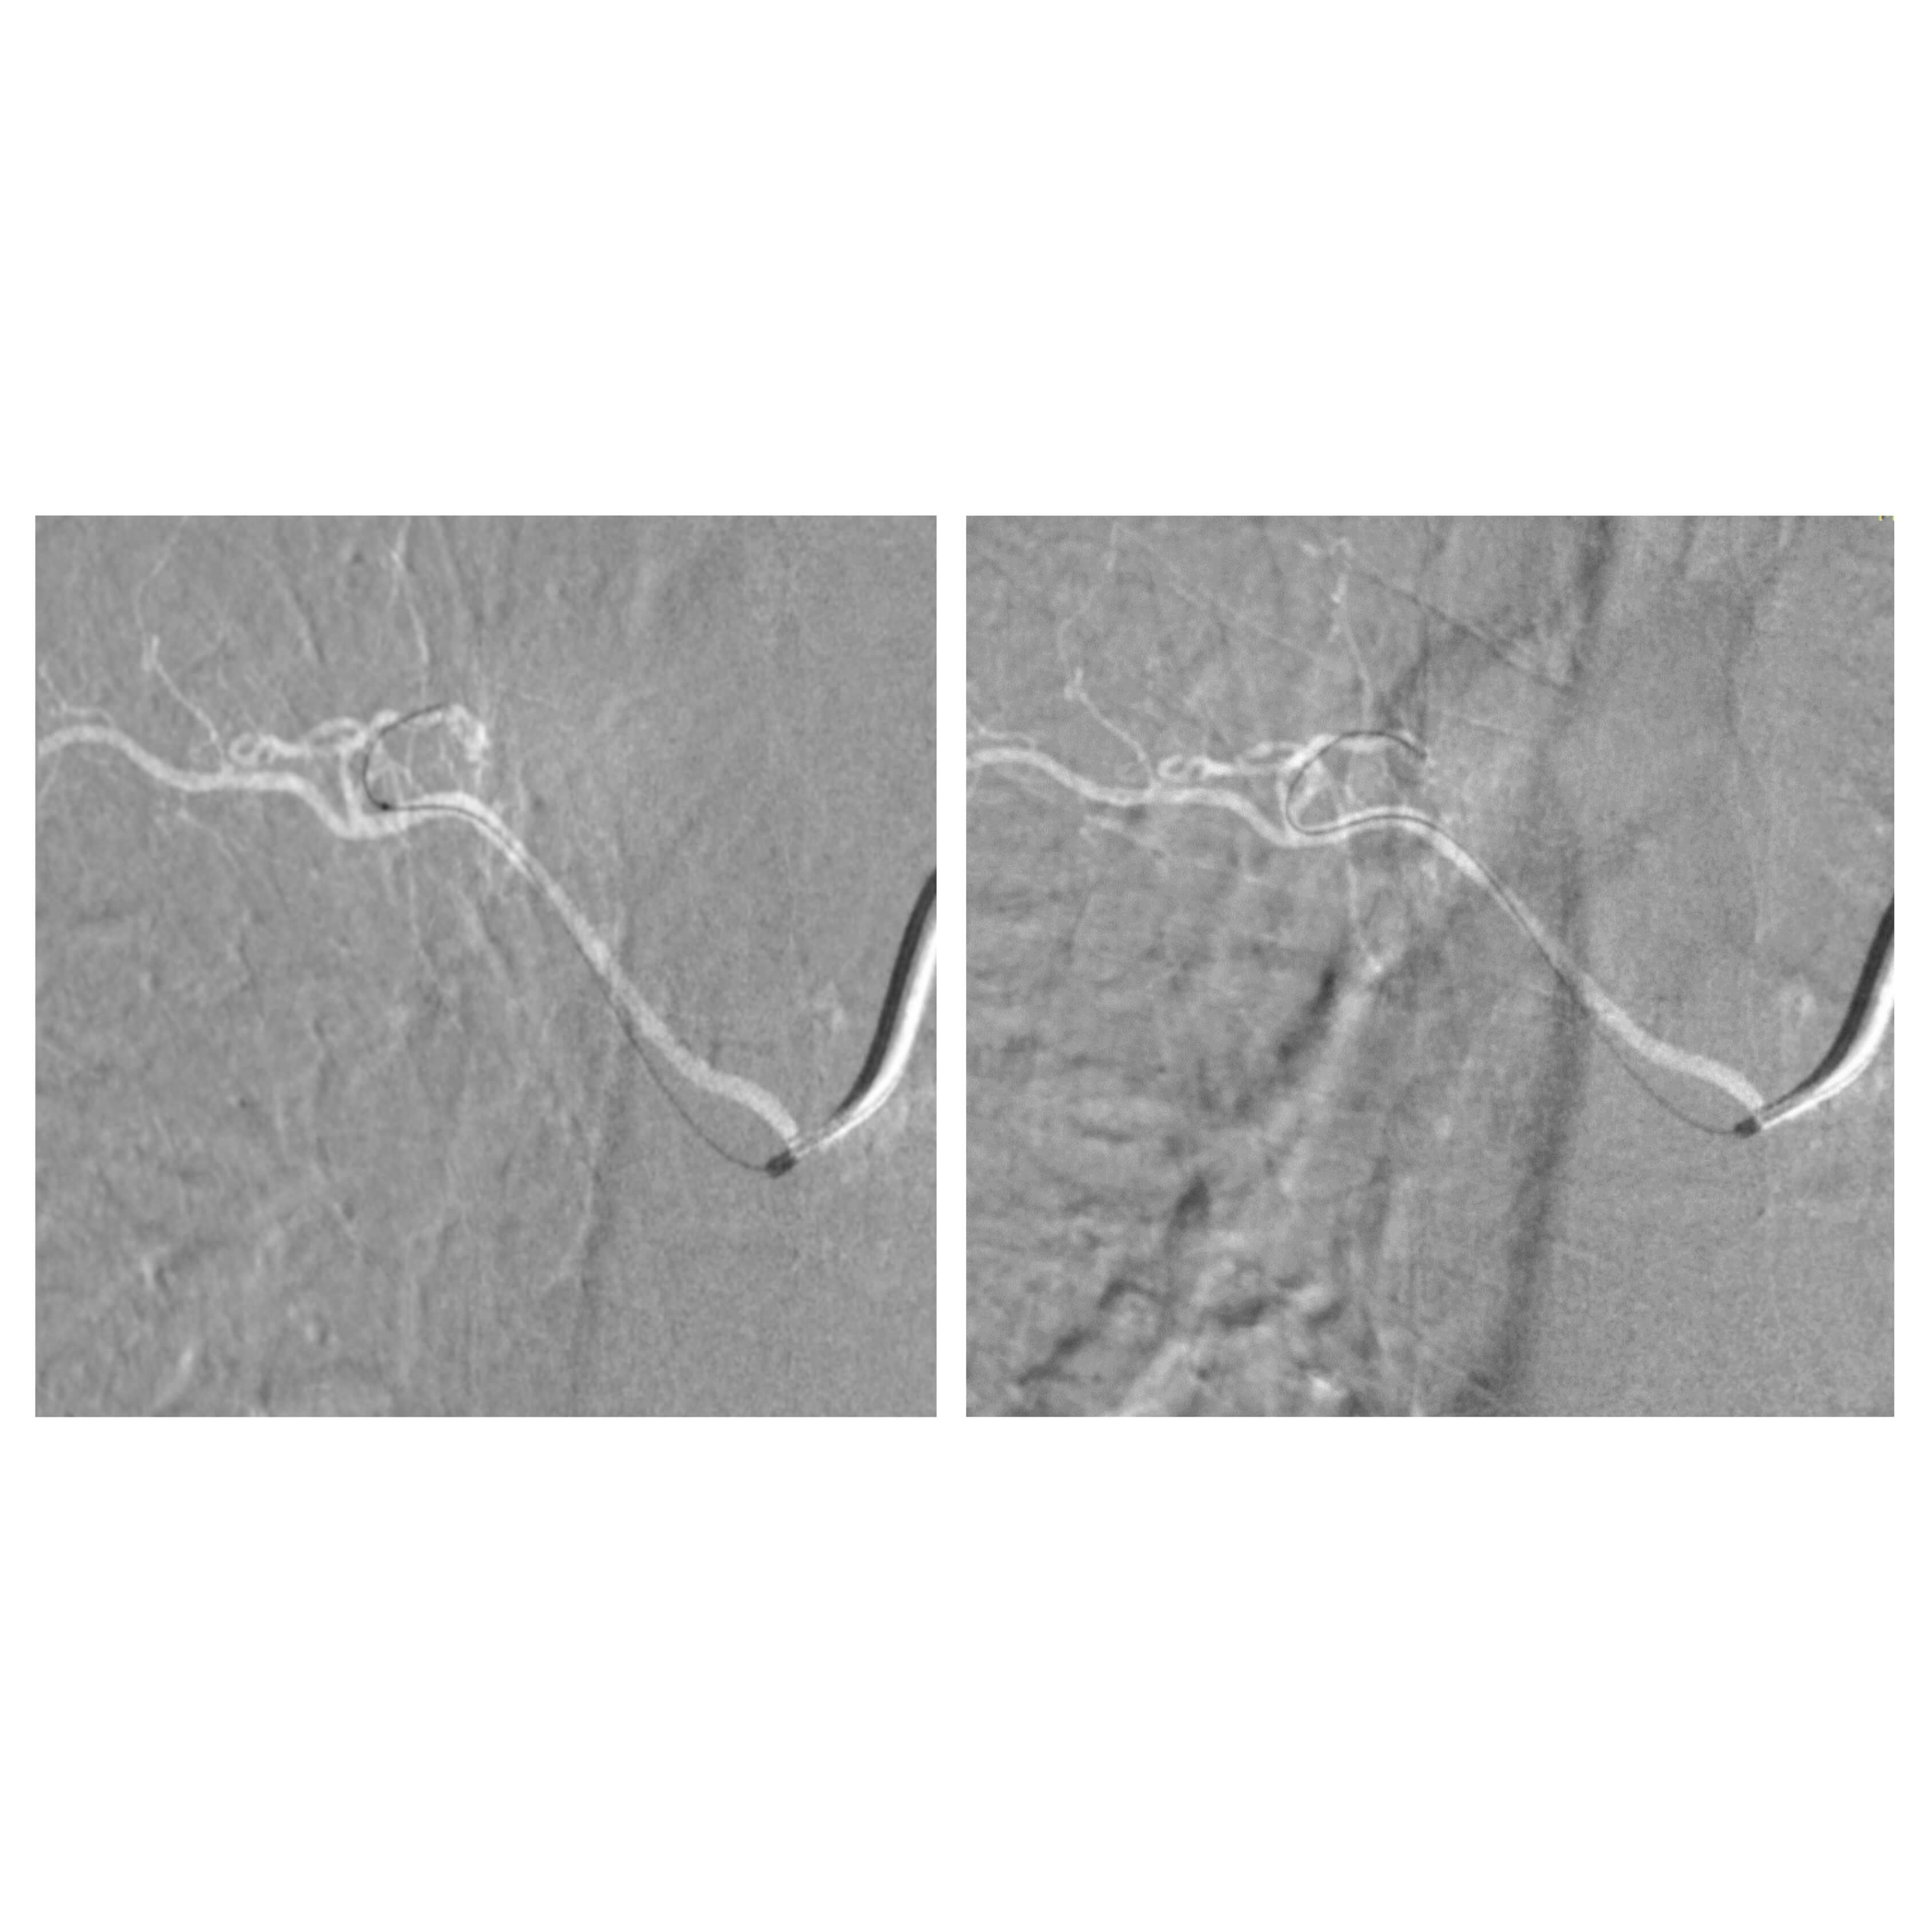

تمكّن الفريق الطبي في وحدة القسطرة بالمستشفى التخصصي، بقيادة الدكتور حازم حبوب استشاري الاشعة التداخلية، من إجراء تداخل طبي متقدم لمعالجة حالة شلل طرفي ناتج عن وجود تشوه شرياني وريدي في النخاع الشوكي، وذلك تحت المراقبة الفسيولوجية العصبية الدقيقة.

وتمت العملية بنجاح من خلال استحضار الإمكانيات الحسية والحركية للمريض أثناء الإجراء، لتفادي أي مضاعفات محتملة. وأسفرت العملية عن تحسن ملحوظ في حالة المريض، حيث أصبح قادراً على المشي بشكل أفضل وبمفرده، إضافة إلى استعادته السيطرة الكاملة على وظائف الجهاز الهضمي.

ويُعد هذا التدخل الأول من نوعه الذي يُنفذ في وحدة القسطرة بالمستشفى، مما يعكس التقدم المستمر في مستوى الرعاية الطبية والتخصصية المقدّمة.